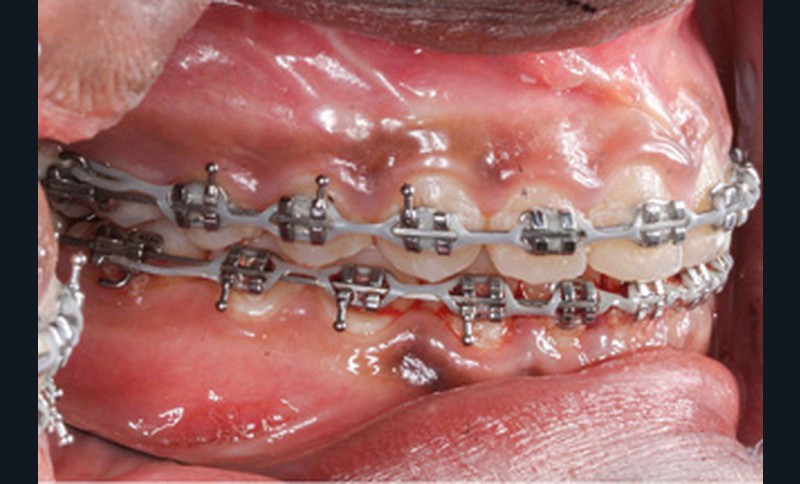

Les finitions orthodontiques d’intercuspidation et de parallèlisation des axes ont été réalisées sur arcs TMA .019x.025 et élastiques interarcades de classe III 6 mm 4 oz puis triangle d’intercuspidation 4 mm 6 oz. Enfin, le dispositif de contention a consisté en fils collés 2-2 maxillaire et 3-3 mandibulaire et gouttière thermoformée maxillaire.